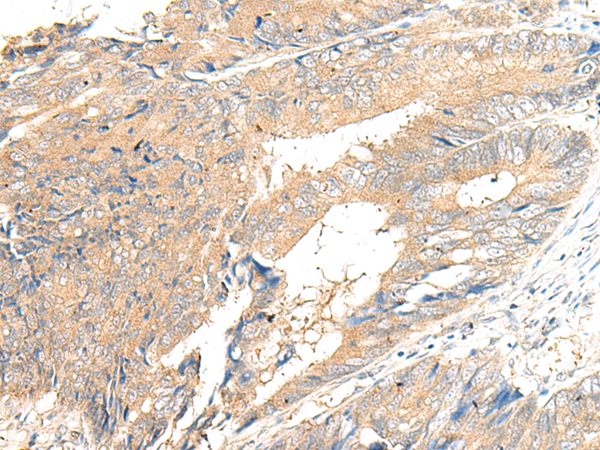

ELISA, IHC

IHC positive control:

Human cervical cancer and Human colorectal cancer

IHC Recommend dilution:

25-100